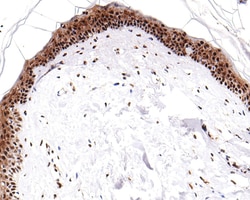

Invitrogen™ Phospho-ATF2 (Thr71) Recombinant Rabbit Monoclonal Antibody (SC05-90)

The transcription factor ATF-2 (also called CRE-BP1) binds to both AP-1 and CRE DNA response elements and is a member of the ATF/CREB family of leucine zipper proteins. ATF-2 interacts with a variety of viral oncoproteins and cellular tumor suppressors and is a target of the SAPK/JNK and p38 MAP kinase signaling pathways. Various forms of cellular stress, including genotoxic agents, inflammatory cytokines and UV irradiation, stimulate the transcriptional activity of ATF-2. Cellular stress activates ATF-2 by phosphorylation of Thr69 and Thr71. Both SAPK and p38 MAPK have been shown to phosphorylate ATF-2 at these sites in vitro and in cells transfected with ATF-2.

| Immunohistochemistry (Paraffin), Western Blot, Immunocytochemistry | |